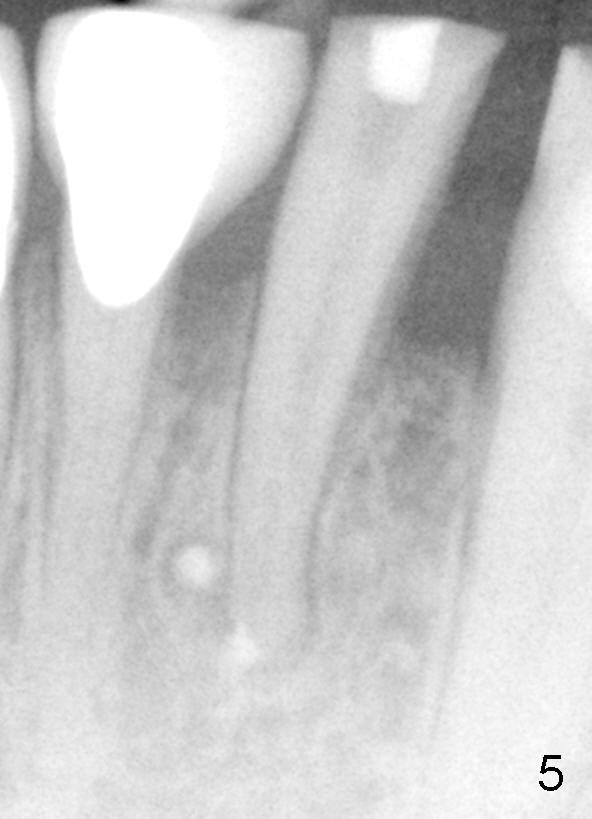

Sixty-two year old Chinese man presented to my office for new patient exam in June 2009. He has history of bruxism and wears night guard (Fig.1). The tooth #25 has incisal composite (*) with mild percussion. PAs show + PARL associated with #25 (Fig.2) and possible missing one canal (Fig.3; arrowheads point to possible 2nd root). RCT retreat was suggested. Extraction and implant were proposed as an alternative. In the next two 6-month appointments, he complained of mild pain in lower front tooth sometimes. RCT retreat was initiated on June 16, 2010. After removing composite, GP was removed with Chloroform and hand files. WL was determined by Root XZ at 15 mm. Debridement was done with hand files until #20 and rotary files until 30/.06 (Fig.4). The second canal was not found. It appears that some of GP was pushed outside of apical constriction (Fig.5 after Cavit). Twelve days later the patient returned to finish RCT retreat. It appears that symptoms improved after initiation of RCT retreat, although percussion is still mild. After removing Cavit and redebridement with #30 hand file, #10 precurved K file was inserted several times at different directions, hopefully getting into 2nd canal, which was not found. RCT filling was finished using AH Plus paste, master cone, lateral condensation with 1 medium fine accessory GP and vertical condensation (Fig.6). Composite build up was done immediately. Six months later, the patient insisted that pain is reduced substantially, but there is still mild percussion. PA shows persistent PARL (Fig.7 with outline with 2nd root (arrowheads)). Twelve months after RCT retreat, the patient is symptom-free, but objectively is not (including mild percussion and slightly enlarging PARL (Fig.8)). The 2nd canal is apparently lightly filled (red arrowhead).